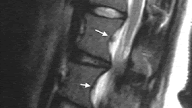

On MRI it is not that easy to find spondylolysis. This is mostly due to more horizontal angle of the fractures compared to vertical angle of the normal facet joints as seen on transversal images. The sagittals are not always that helpful as well. The clue is that spondylolysis looks like 'additional joint' that should not be there. Note on the images above spondylolysis as well as normal facet joint with cartilage seen on the last image (long arrow). This is the same patient as shown on CT therefore it is good to compare those two diagnostic methods.